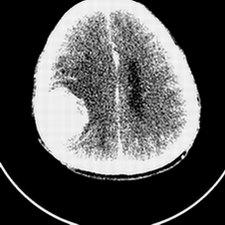

标题: CT25808:男,48岁,头痛多年,近段时间头痛加重伴步态不稳 [打印本页]

标题: CT25808:男,48岁,头痛多年,近段时间头痛加重伴步态不稳

平扫:右颞顶叶病灶呈等低密度伴大面积水肿,脑室受压变形。增强:病灶显著强化。考虑淋巴瘤或黑色素瘤。

1)不排除黑色素瘤可能;建议行mri检查。2)大脑镰下疝。3)脑积水(梗阻性)。